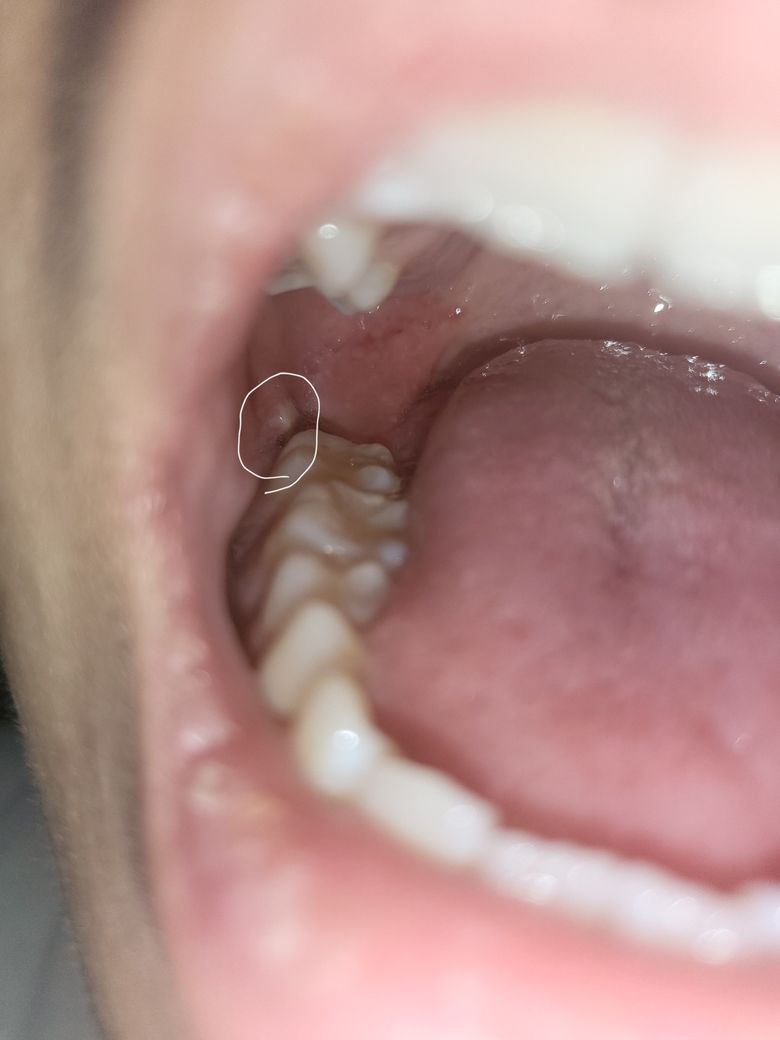

사랑니 뽑고 하얀색이 보이는데 뭔가요?

사일전에 오른쪽 위아래 사랑니를 뽑았고 위쪽에서 피가 안멈춰서 응급실 갔다가 이제는 진정이 됬는데

지금은 아래쪽에서 흰색이 보이고 조금 욱씬거리는것 같아요

병원을 가야될까요?

잇몸이 눌려서 생긴현상입니다 큰 문제가 잇는건 아니니 너무 걱정하지 않으셔도 될것같습니다.

발치 후 지속된 출혈과는 별개로 염증이 생긴 것 같습니다. 처방받은 항생제 복용하시면 곧 괜찮아질 것으로 보입니다.